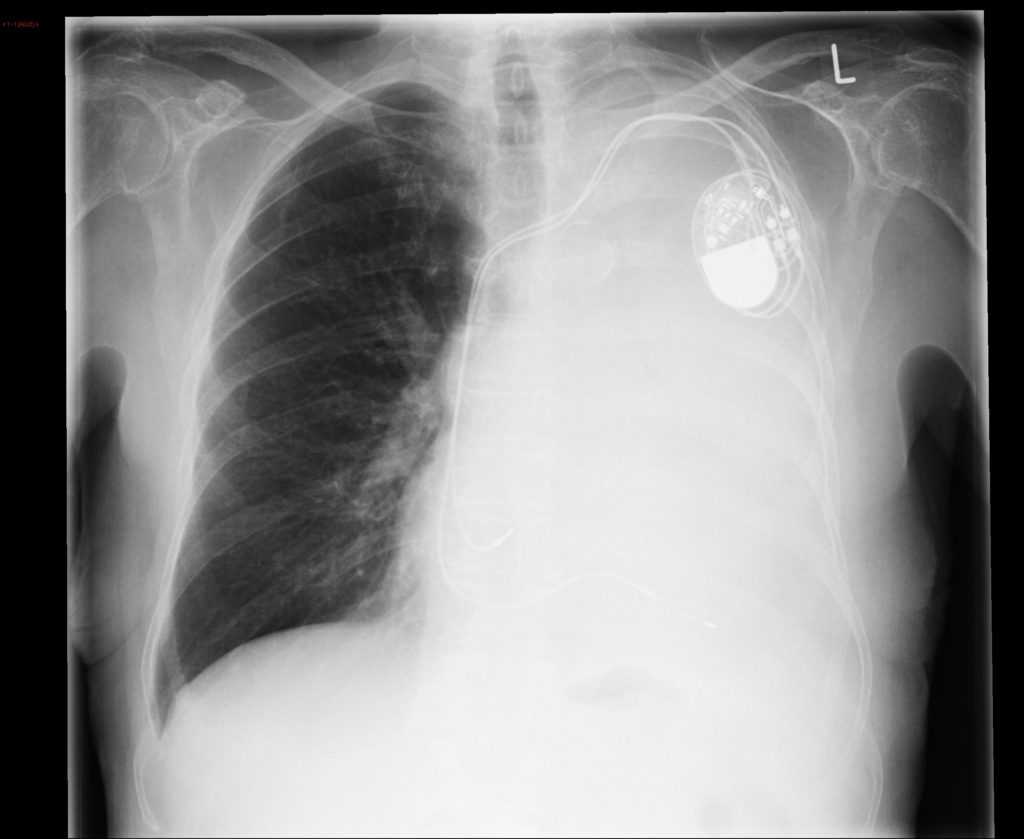

Тотальный ателектаз легкого на рентгене

Тотальный ателектаз легкого, обнаруженный на рентгенограмме, указывает на полное или почти полное коллапсирование легочной ткани. Ателектаз может возникать из-за различных причин, включая блокировку бронхов, компрессию легкого, нарушение дыхательных движений и другие факторы.

Ателектаз обычно представляет собой признак основного заболевания или состояния, такого как застойная пневмония, опухоль, большой объем жидкости в плевральной полости (гидроторакс), пневмоторакс или другие проблемы с дыхательной системой. Для определения точной причины тотального ателектаза требуется более подробное клиническое обследование, включая анамнез, физикальное обследование, лабораторные и другие диагностические исследования.

Важно обратиться к врачу по рентгенологии для более точной интерпретации рентгеновского снимка и определения причины тотального ателектаза. Только квалифицированный медицинский специалист сможет предоставить конкретную информацию и рекомендации на основе клинической картины пациента